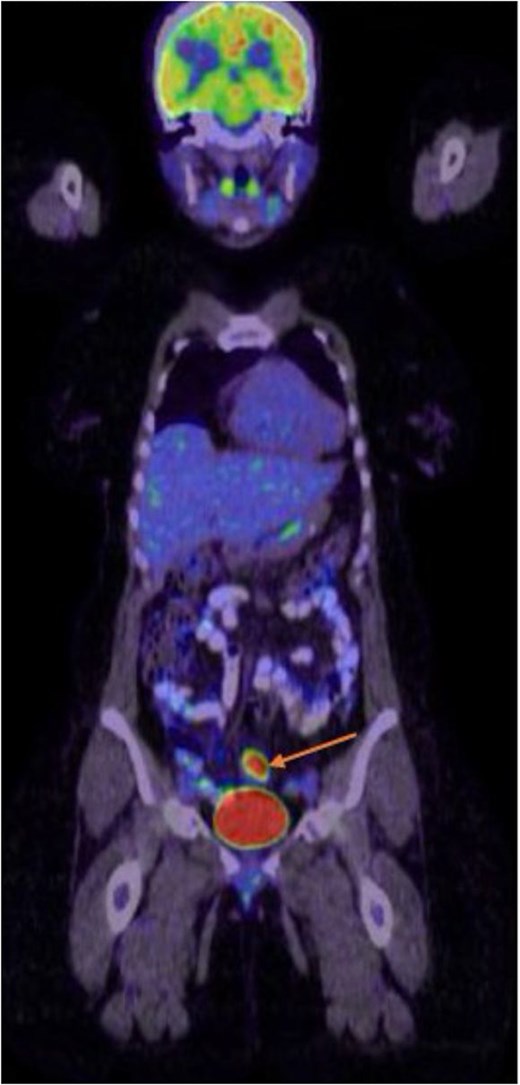

The case was discussed in the neuro-oncology multidisciplinary team (MDT) meeting, which recommended colonoscopy and stereotactic radiosurgery (SRS) of the tumor bed. SRS was performed with 20 Gray (Gy) in a fraction. Upper and lower endoscopies were performed which showed a sigmoid tumor (Fig. 2), endoscopic biopsy confirmed a moderately differentiated adenocarcinoma. Staging CT scans of the chest and abdomen along with positron emission tomography (PET) CT showed no metastasis (Fig. 3). Baseline tumor markers, including carcinoembryonic antigen (CEA) and cancer antigen (CA19-9), were within normal range. She was reviewed at the colorectal MDT and planned for neoadjuvant chemotherapy (leucovorin, Fluorouracil, and Oxaliplatin (FOLFOX) 4 cycles), followed by surgical resection of the primary sigmoid tumor. The patient completed her chemotherapy cycles and follow-up brain imaging revealed no new brain lesions. She subsequently underwent sigmoid colectomy with uneventful recovery.

Whole body PET CT scan showing sigmoid colonic tumor with intense metabolic activity. No detectable locoregional lymph nodal or distant metastasis.